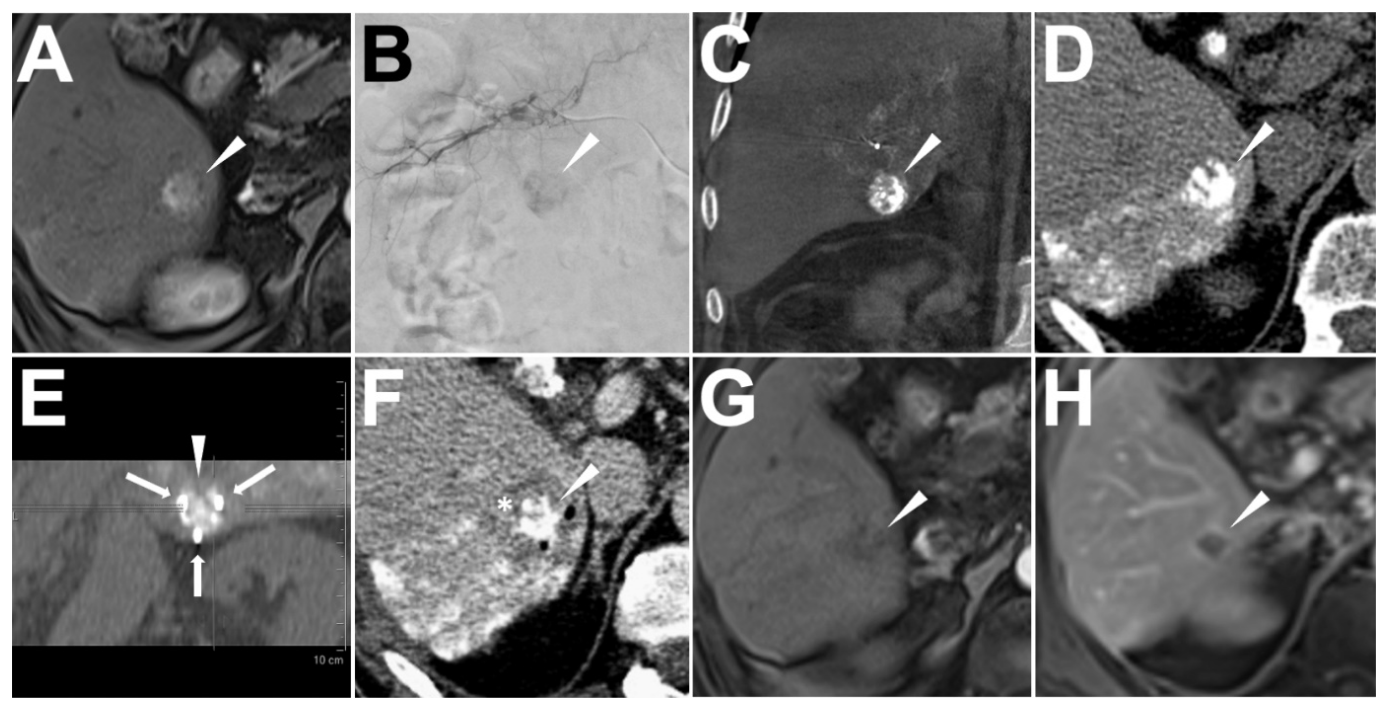

2.3. Ethiodized Oil Tumor Marking Procedure

2.4. IRE Treatment

3.2. Success of Ethiodized Oil Tumor Marking

3.4. Success of IRE

3.5. Adverse Events and Follow-Up